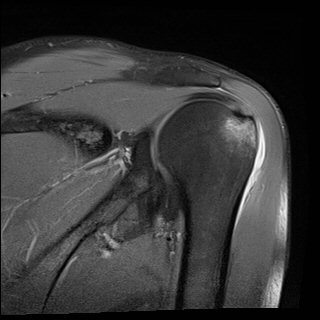

´ë°áÀý °ß¿­°ñÀý¿¡ ÀÏÄ¡ÇÏ´Â ¼Ò°ß(»çÁø 8, 9)

´ë°áÀýÀÇ ¹Ì¼¼ÇÑ °ß¿­°ñÀýÀº ¹æ»ç¼±°Ë»ç¿¡¼­ È®ÀεÇÁö ¾Ê´Â´Ù.

±×·¯³ª ¼÷·ÃµÈ Àǻ簡 ½ÃÇàÇÏ´Â ÃÊÀ½ÆÄ°Ë»ç¿¡¼­´Â °ñÀýÀ» È®ÀÎÇÒ ¼ö ÀÖ´Ù.